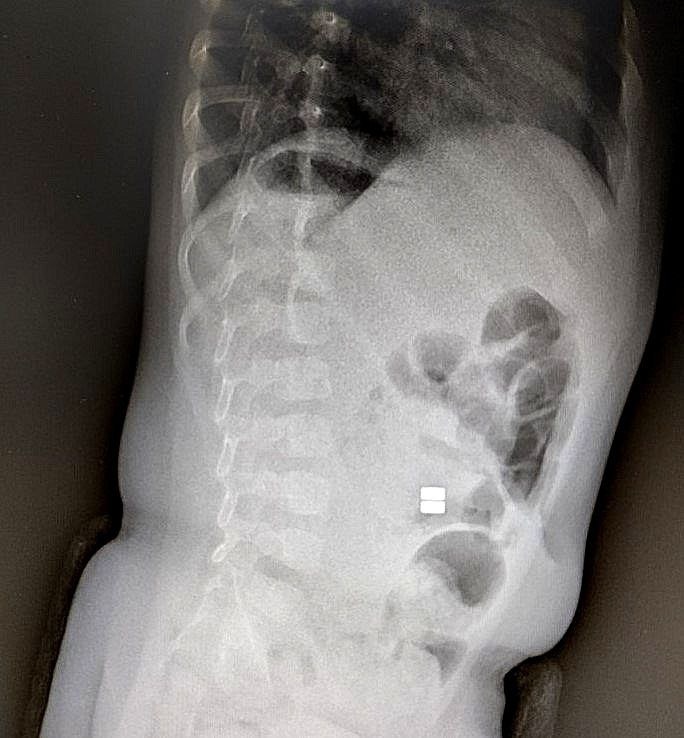

Диагностика затруднительна, так как, если родители не сообщают о проглатывании инородных тел, диагноз ставится с опозданием. Назначить рентгенологическое исследование с лучевой нагрузкой можно только при наличии конкретных показаний, которые обычно проявляются уже на стадии развития серьезных осложнений.

Заместитель главного врача по хирургии, детский врач-хирург Детской областной больницы Наталья Смирнова указывает, что магниты имеют колоссальную силу сцепления, потому их проглатывание приводит к сдавливанию стенок кишечника между магнитами. Как следствие, нарушается кровоснабжение тканей (ишемия). Возникают серьезные последствия, включая перфорации кишечника с перитонитом или непроходимость. Проблема требует срочного хирургического вмешательства и может закончиться смертью.

Фото министерства здравоохранения Амурской области